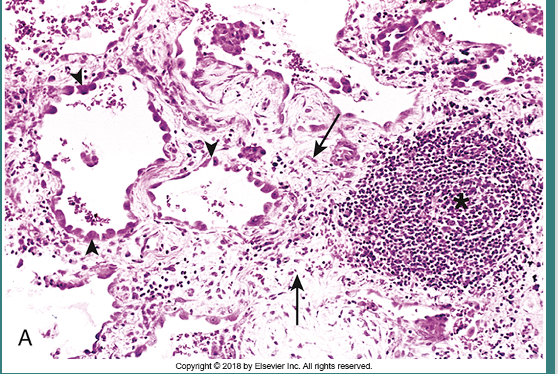

Tuberculous with granulomas